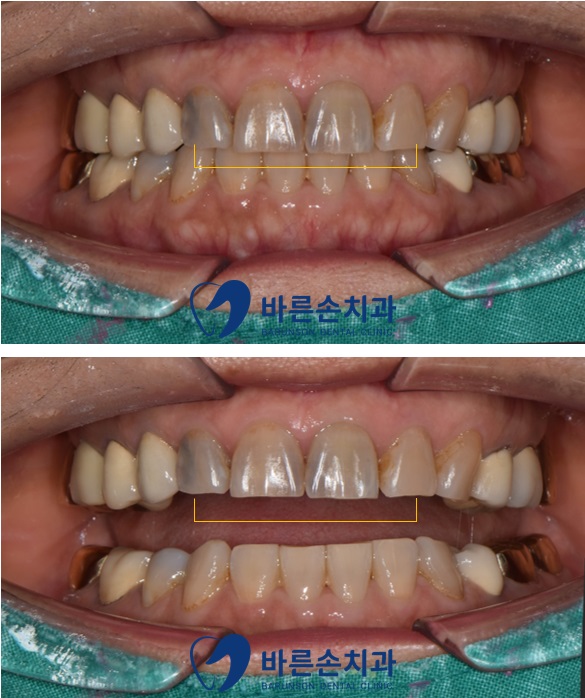

디자인 2를 선택하셔서,

그대로 보철물을 제작 하고,

세팅 후 모습입니다.

색깔, 모양 잘 어울려서 붙이고 진료를 마무리 했습니다.